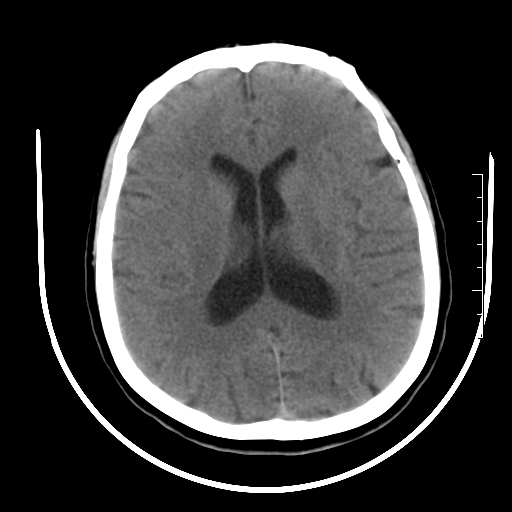

标题: CT27880:f、55y,头痛。 [打印本页]

标题: CT27880:f、55y,头痛。

考虑左侧顶部镰旁脑膜瘤;建议行ct增强扫描检查。

考虑左侧顶部镰旁脑膜瘤,建议行ct增强扫描检查。

考虑左侧顶部镰旁脑膜瘤;建议行ct增强扫描检查

大脑镰旁脑膜瘤可能,建议增强或mri

左侧顶部镰旁脑膜瘤,增强